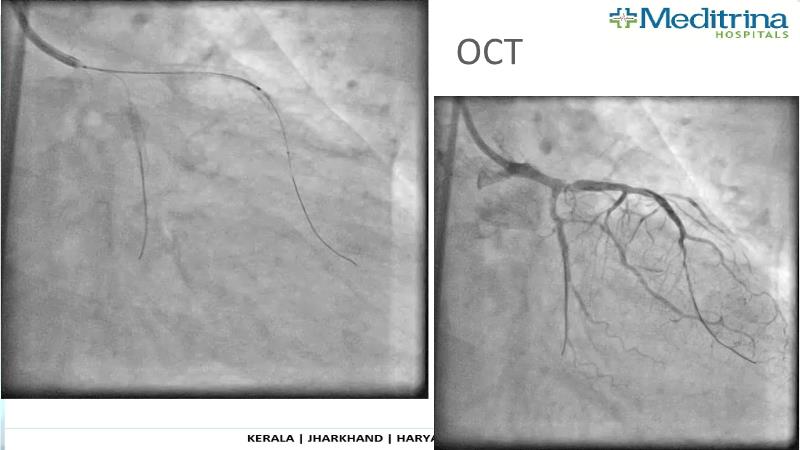

- To define the use of OCT in PCI of complex coronary lesions